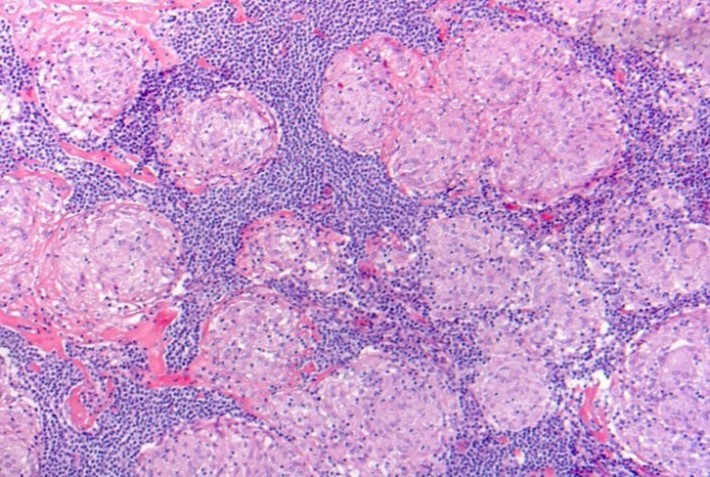

Figur 1: Velformede epiteloidcellegranulomer i lymfeknudebiopsi.

Den granulomatøse inflammation reguleres ved et komplekst samspil af immunkompetente celler (T-lymfocytter, makrofager, B-lymfocytter m.fl.), som interagerer gennem frigørelse af cytokiner og kemokiner. Det viser sig i lungerne initialt som en lymfocytær alveolitis. Gennem proliferation af makrofager, transformation til epithelioidceller og fusion til flerkernede kæmpeceller dannes de sarkoide granulomer.

Granulomet er en metabolisk aktiv struktur, som danner angiotensin konverterende enzym (ACE), 1-α-hydroxylase og en række cytokiner. Blandt disse spiller specielt interferon-γ og TNF-α en afgørende rolle for dannelse af granulomer.